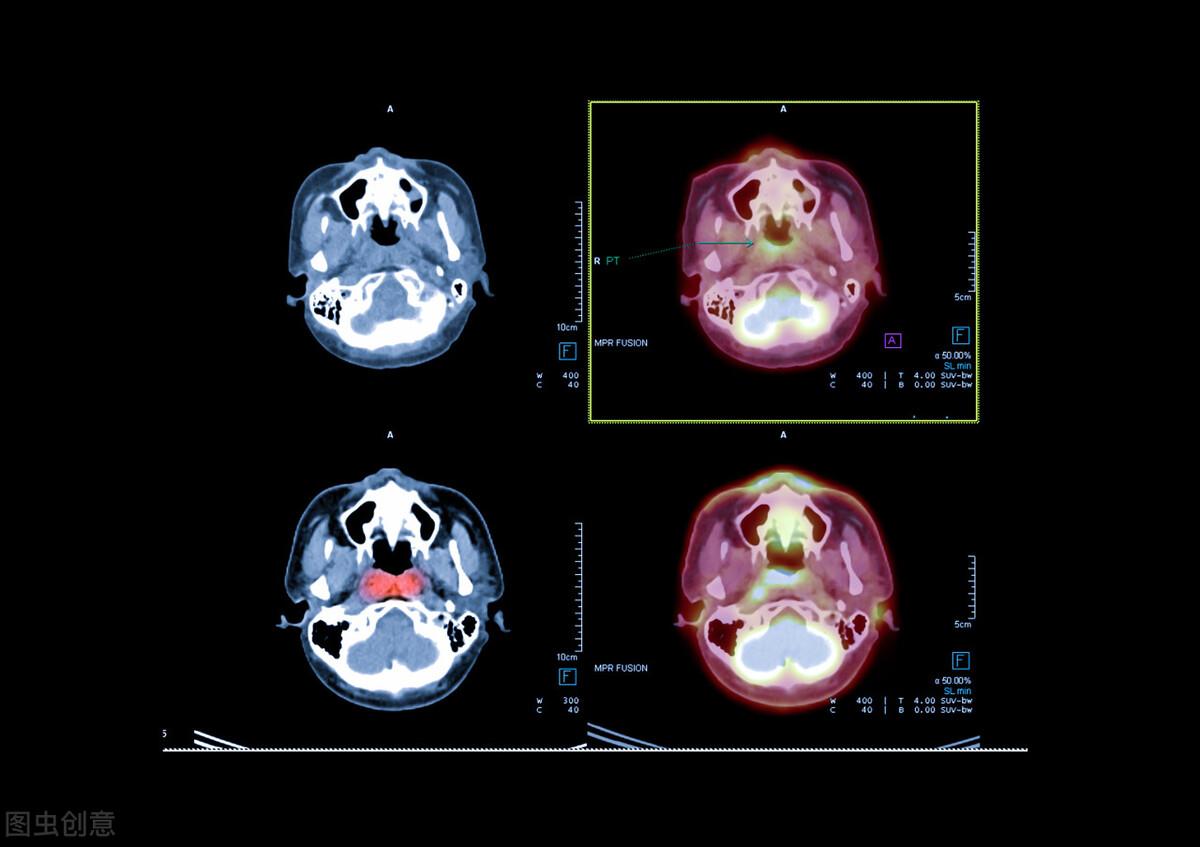

就在近期43岁的鼻咽癌患者刘先生刚完成了PET—CT复查,这次复查已是质子治疗后的35个月(近3年)。

复查结果提示:鼻咽癌放疗后:鼻咽左侧壁黏膜代谢活跃,疑似炎性病变;余鼻咽各壁黏膜未见明显增厚,代谢未见明显异常。未见明显肿瘤征象。

幸运的是在治疗后的多次复查中,均未见复发征象!这也让质子治疗在抗癌的历程中,增添精彩的一笔!